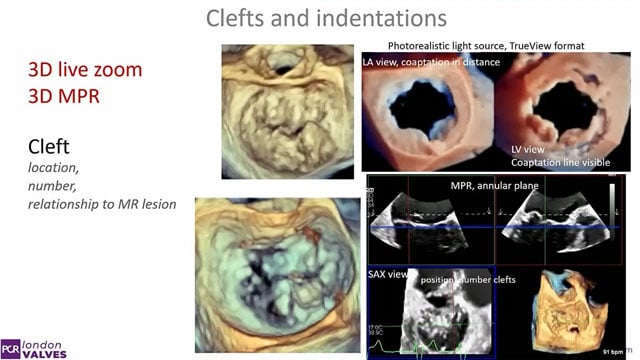

Mitral TEER masterclass

16 Nov 2025 – From PCR London Valves 2025

This masterclass provides a comprehensive framework for mitral Transcatheter Edge-to-Edge Repair (TEER), covering imaging-guided procedural planning, device selection, and deployment. It emphasizes recognition of anatomical challenges and strategies to avoid and manage complications such as single leaflet device attachment, ensuring optimal outcomes.